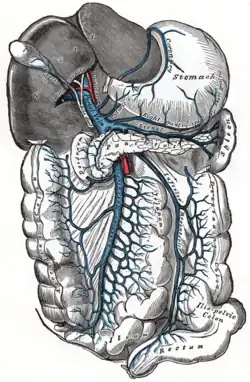

| The portal vein and its tributaries | |

Portal hypertension is defined as increased portal venous pressure, with a hepatic venous pressure gradient greater than 5 mmHg.[3][4] Normal portal pressure is 1-4mmHg; clinically insignificant portal hypertension is present at portal pressures 5-9mmHg; clinically significant portal hypertension is present at portal pressures greater than 10mmHg.[5] The portal vein and its branches supply most of the blood and nutrients from the intestine to the liver.[6]